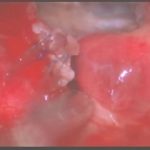

術中写真

摘出 前

摘出 中

摘出 後